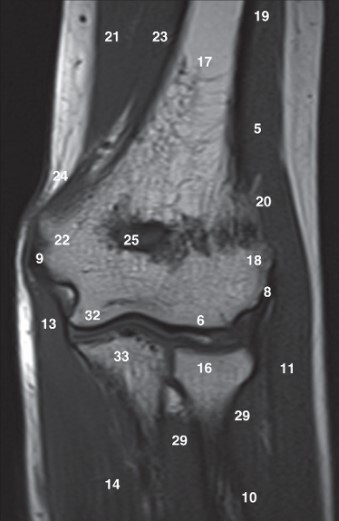

Label 6,16,17,18,22,25,32

A

6=Capitulum of lt. humerus

16=Head of lt. radius

17=Lt. Humerus

18=Lateral condyle (lt. humerus)

22=Medial condyle (rt. humerus)

25=Olecranon fossa of lt. humerus

32=Trochlea of lt. humerus